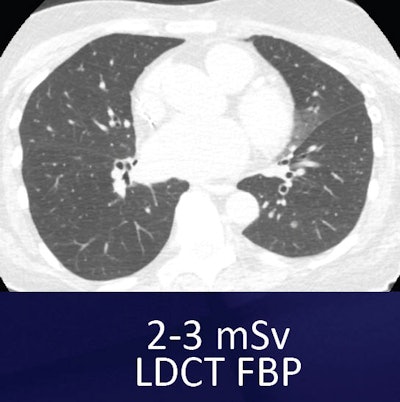

Small nodule in left lung base can be seen both in the standard low-dose filtered back projection (FBP) technique (above) and the ultralow-dose MBIR technique (below). However, the images look inherently different, which may take some getting used to. All images courtesy of Dr. Ella Kazerooni.

For example, one commercially available MBIR protocol (Veo, GE Healthcare) has shown an impressive ability to reduce noise and improve contrast and spatial resolution, she said. The technique, cleared by the U.S. Food and Drug Administration (FDA) in 2011, uses advanced modeling of system statistics and optics to increase spatial and contrast resolution while permitting vastly lower radiation doses -- as low as 0.2 mSv -- in the lungs.